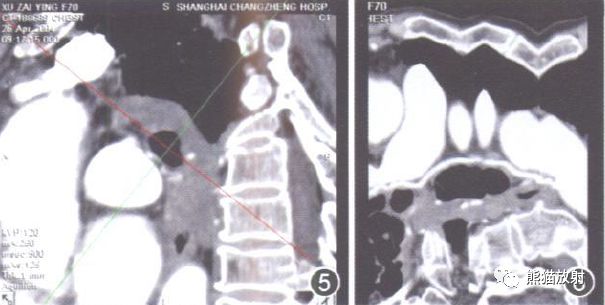

图1A、B 前后位及后前位VR示BA为R1L1型, R1源自右侧肋间后动脉, 呈直线型沿右主支气管后壁走行, 随支气管的分支而分支,L1源自降主动脉前壁, 沿左主支气管上壁走行。

图2A、B 前后位及后前位VR示BA为R1L1, R1源自右侧肋间后动脉, 沿途发出分支呈树枝状分布至右肺各叶,L1源自降主动脉前壁, 发出后即分为2支, 上支沿左主支气管上壁走行, 下支同时行经左主支气管后壁及下壁。